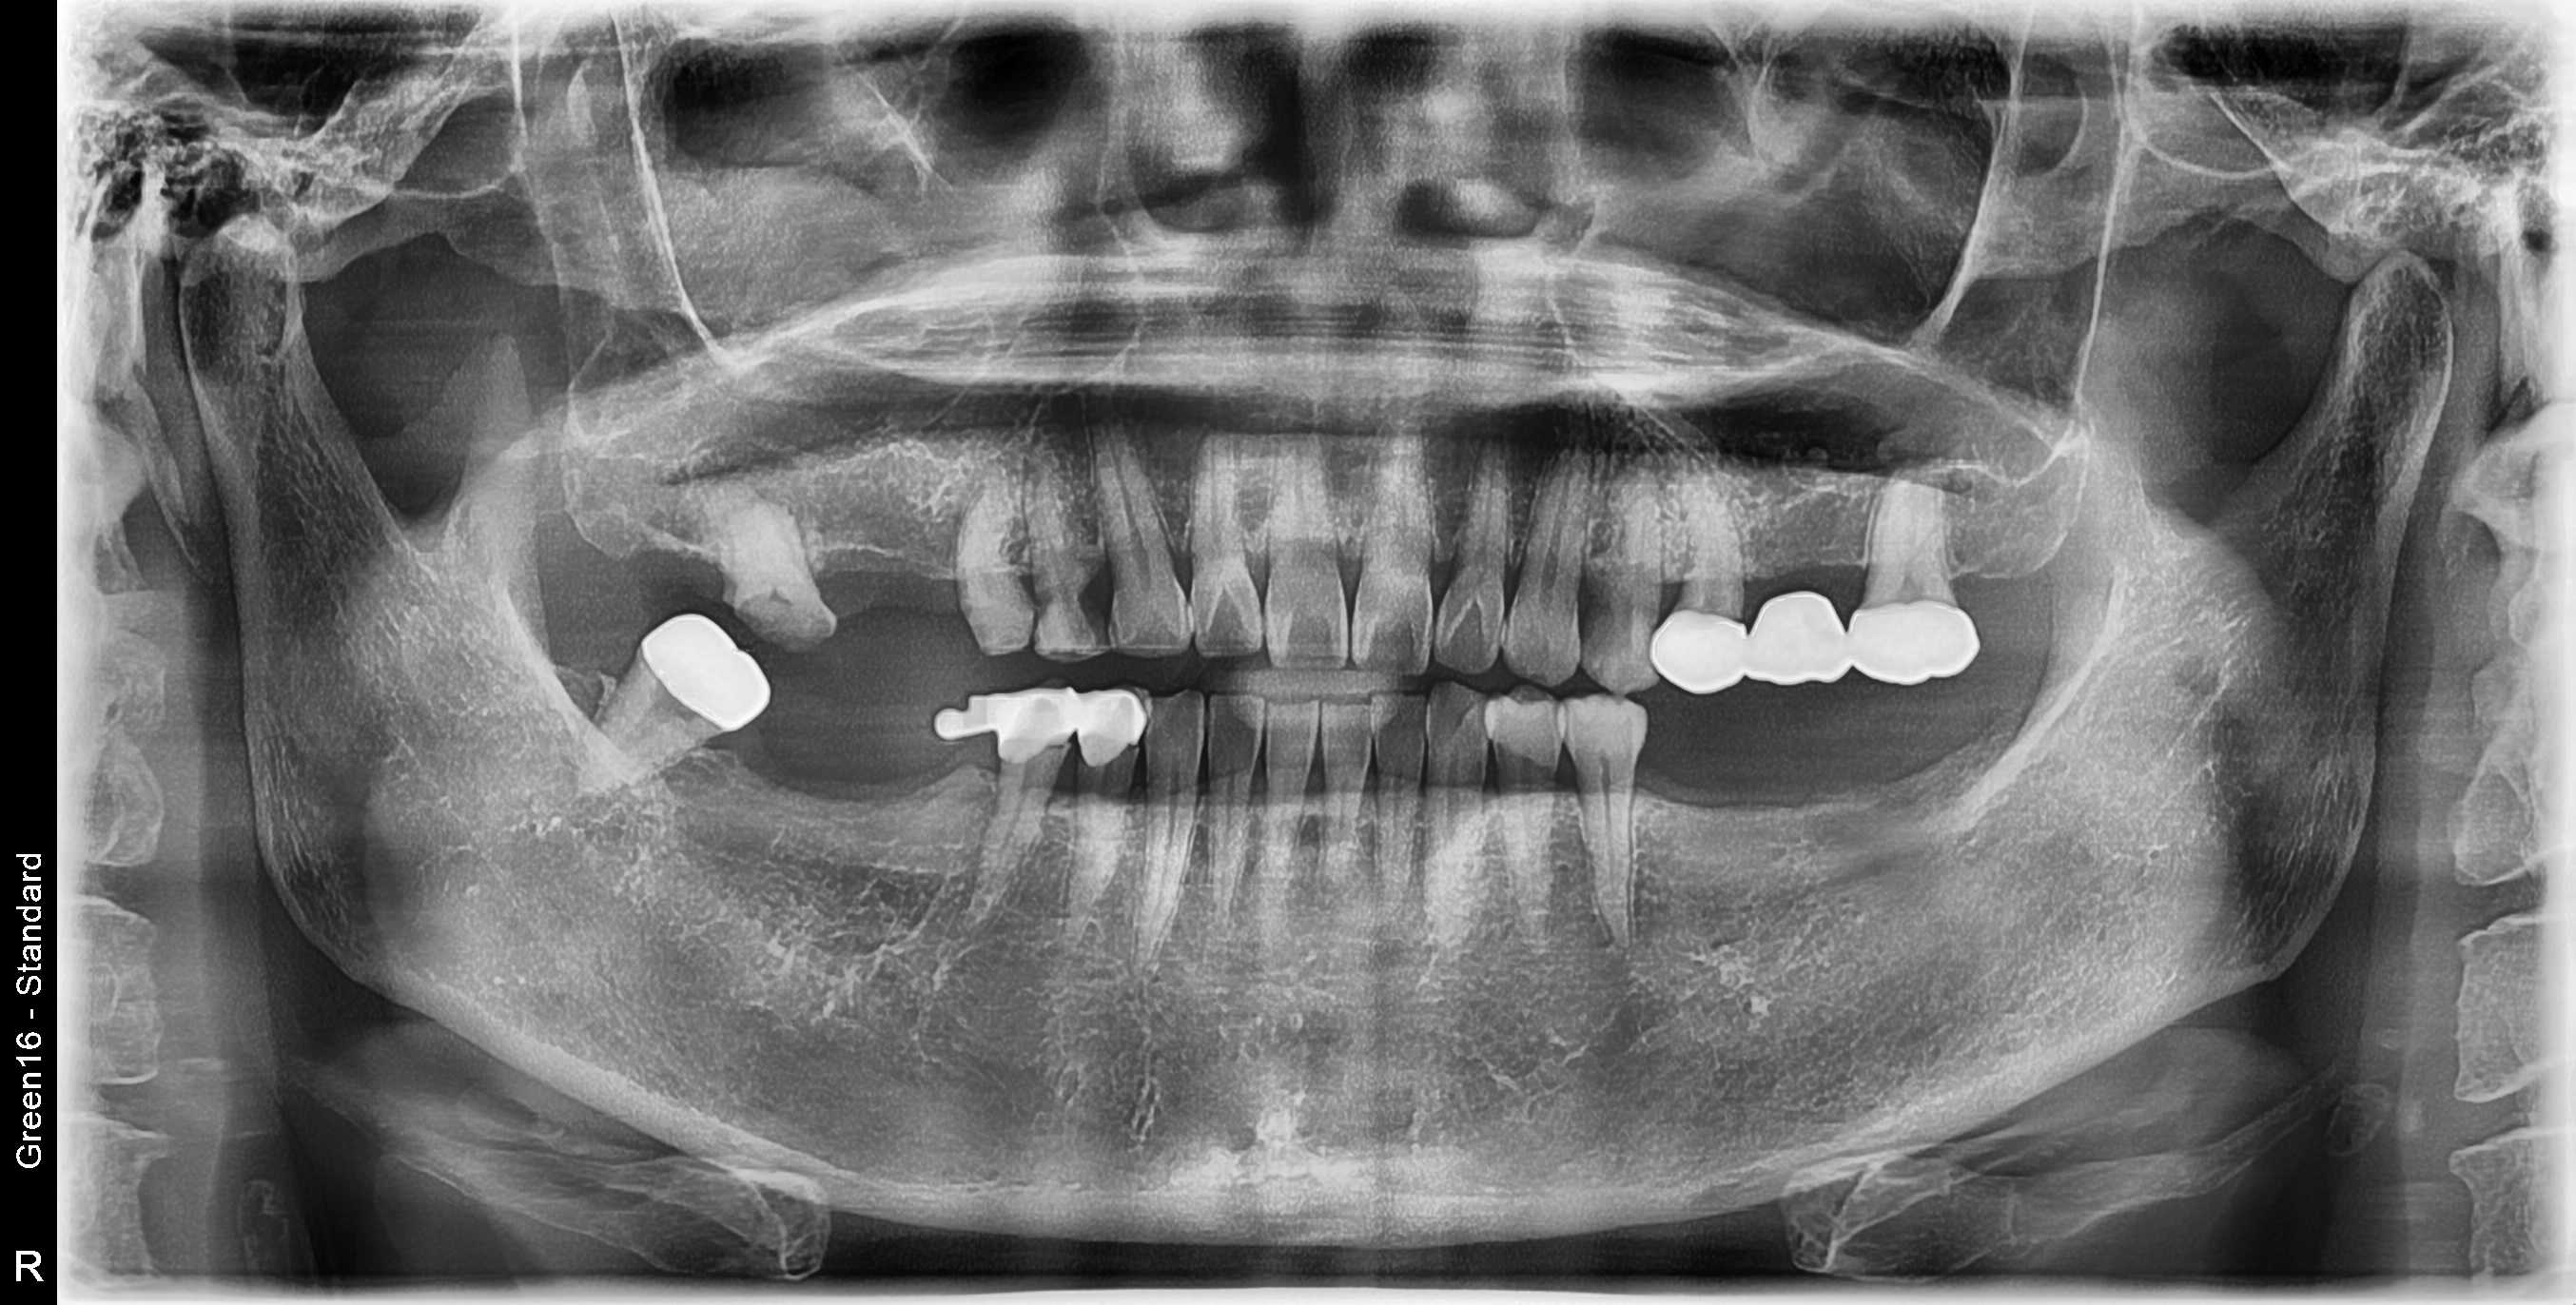

수술 전

수술 후

좌측 임플란트 흔들림 재수술 사례

전후사진

우측 임플란트 식립 사례